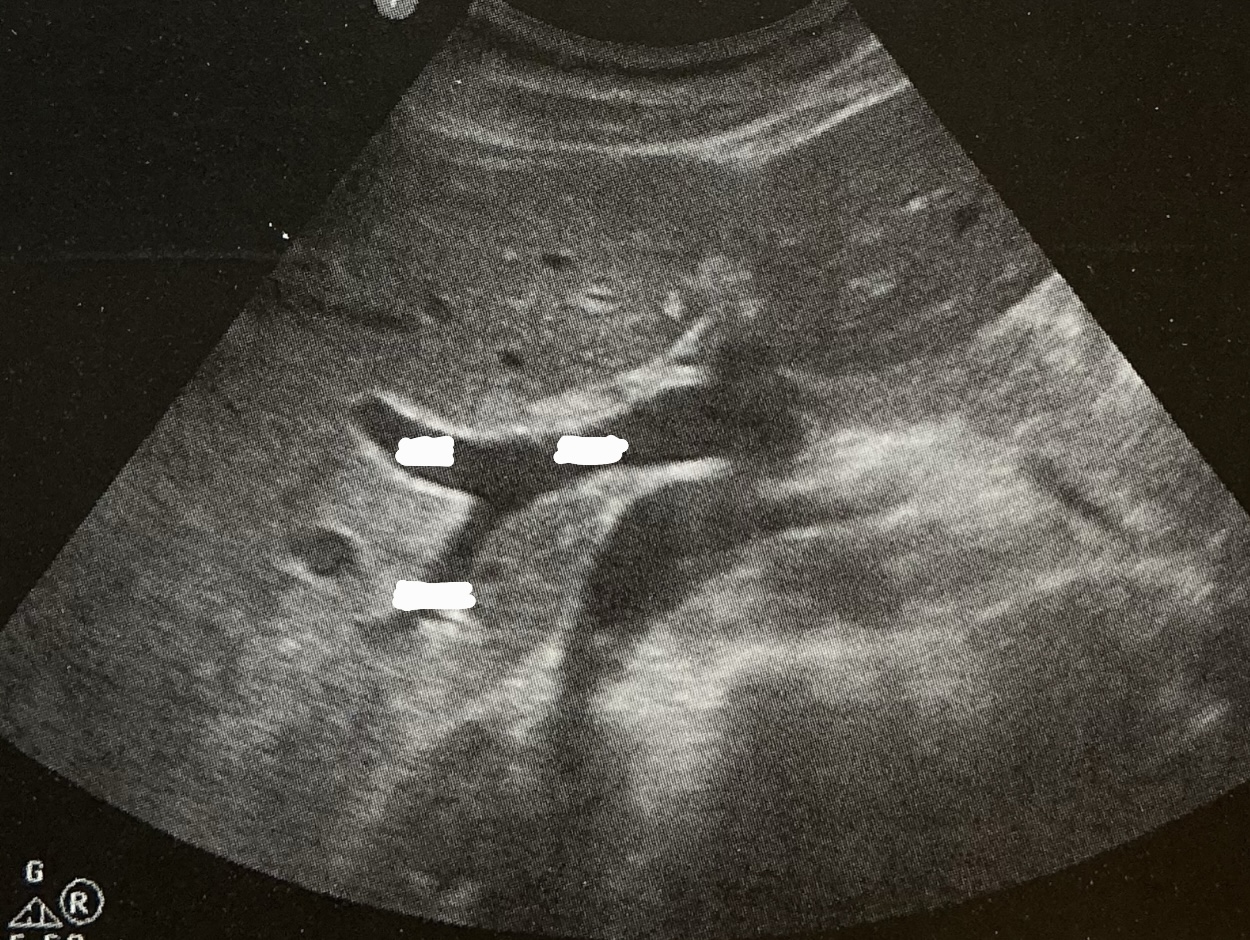

Label this image

Describe the portal triad which is found in each of the 8 segments. What are the segmental divisions based on?

1) hepatic artery: ventral and medial

2) portal vein: dorsal

3) bile duct: ventral and lateral

hepatic veins provide boundary and portal veins